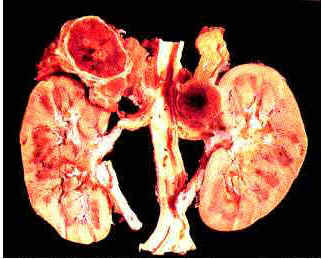

12. Phenochomocytoma picture (http://health-pictures.com/pheochromocytoma.htm); Geneva Foundation of Medical Education and Research, Pheochromocytoma, http://www.gfmer.ch/selected_images_v2/detail_list.php?cat1=1&cat2=113&cat3=22&cat4=2&stype=n .

13. Brown H, Goldberg PA, Selter JG, Cabin HS, Marieb NJ, Udelsman R and Setaro JF Hemorrhagic Pheochromocytoma Associated with Systemic Corticosteroid Therapy and Presenting as Myocardial Infarction with Severe Hypertension. Clinical Case Seminar, J Clin Endocrinol Metab 2005 90: 563-569. (http://jcem.endojournals.org/cgi/content/full/90/1/563).